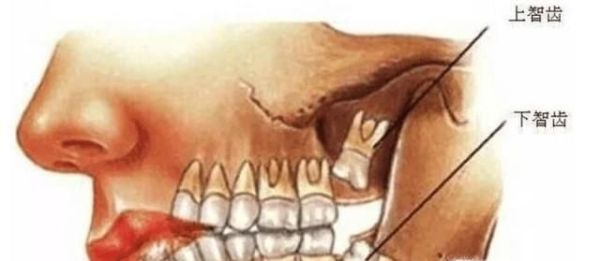

操作方法01、首先,长了智齿的话,如果智齿靠近我们的神经的话,那么这样的智齿是不能拔的,因为如果拔的话,一旦碰到神经的话,那么对我们的身体伤害是巨大的,一般医生也不会建议我们拔的,我们需要定期清理干净我们的智齿处。

04、最后,我们需要根据实际情况来确定是否需要拔掉智齿,如果智齿直接顶到另一颗牙齿生长的话,这样的智齿我们也是需要拔除的,不然我们的整体牙齿都会有一定的伤害,这是必须要拔的。